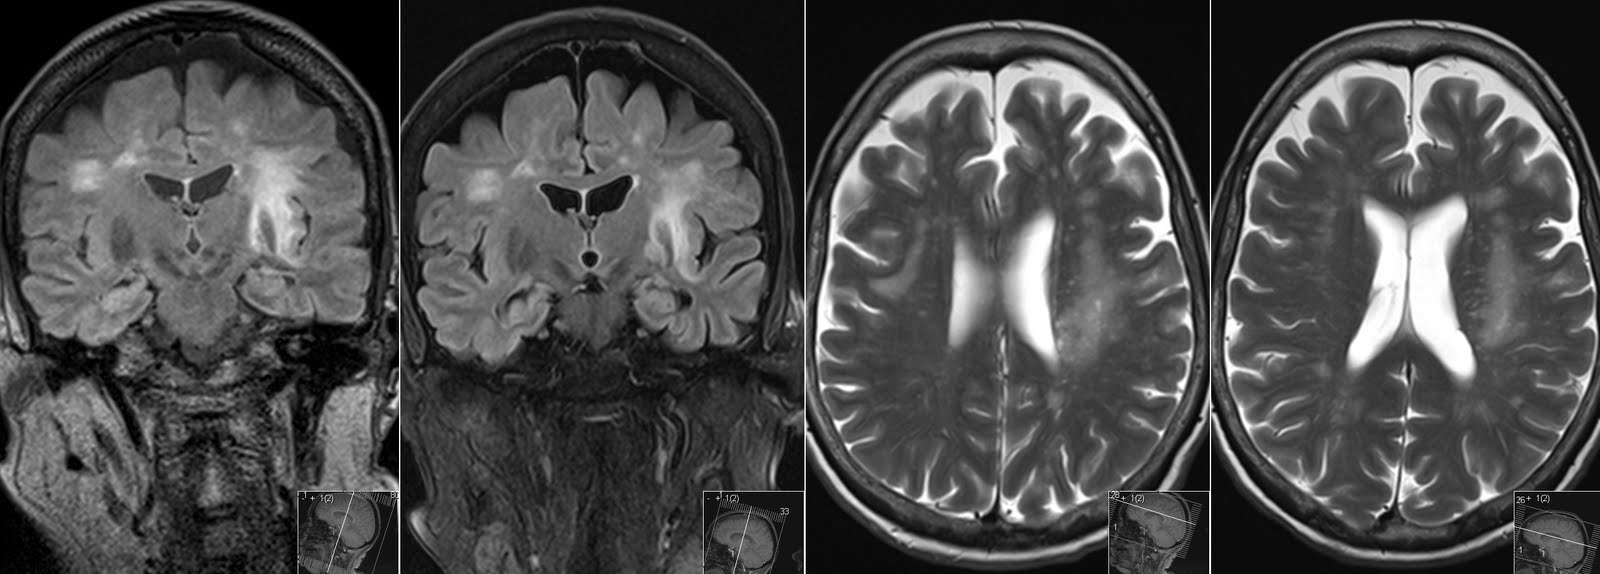

Атрофическая деменция

Атрофическая деменция 114 фотографий